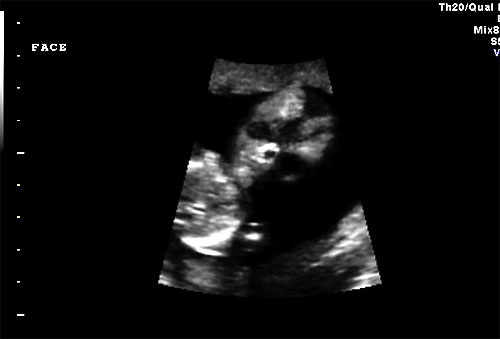

Normal 16 week fetal face |

Normal 16 week sagittal view of face |